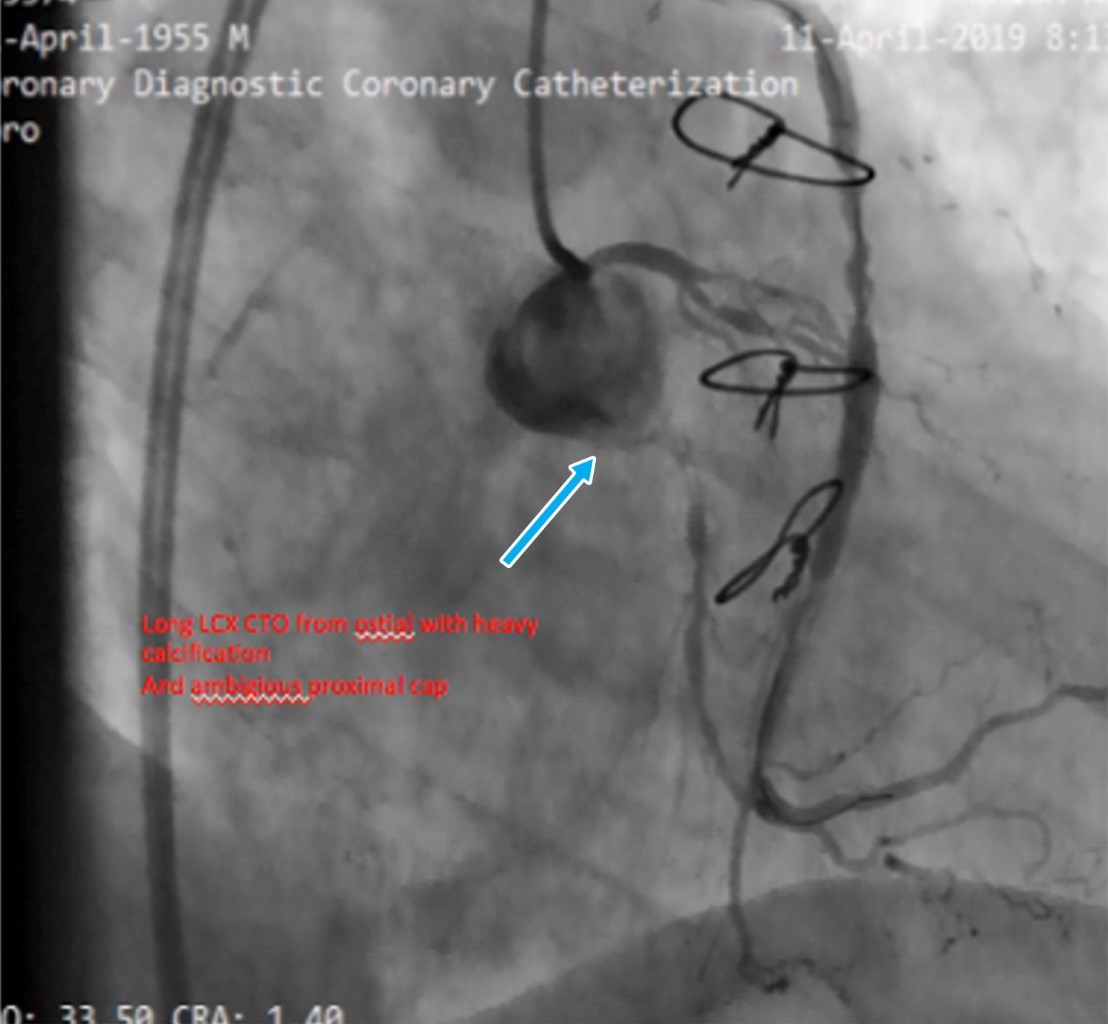

Reportamos el caso de un hombre de 78 años con antecedentes de cirugía de revascularización coronaria (CRC) e intervención coronaria percutánea (ICP) del injerto de vena safena (IVS) a la arteria marginal obtusa (MO). El paciente presentó síndrome coronario agudo y fue derivado a atención terciaria después de que la angiografía coronaria revelara reestenosis intrastent en una IVS trombótica, junto con oclusión total crónica (OTC) de la arteria circunfleja izquierda (CI). Nuestro plan inicial fue la intervención de IVS a MO debido a reestenosis del stent y trombosis. Durante el procedimiento, una rotura de balón resultó en disección y hematoma. Como intervención de rescate, se realizó stent nativo en la CI con OTC, seguido de oclusión con coil de la IVS. Surgieron complicaciones cuando el coil se desprendió y fragmentó, lo que llevó a la embolización de una partícula en la aorta descendente y la otra en la arteria femoral. Ambos fragmentos se recuperaron con éxito mediante un lazo. Este caso destaca la complejidad del manejo de las complicaciones de la ICP relacionadas con la IVS y la importancia de manipular cuidadosamente el dispositivo durante los procedimientos de colocación de la bobina.

Figura 4